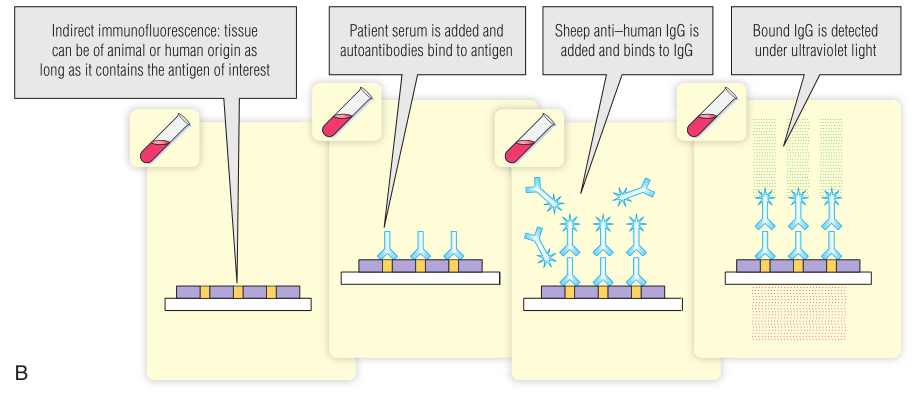

免疫荧光使用的是荧光化合物(荧光素)共价连接的抗体。免疫学家广泛使用的一种荧光化合物是异硫氰酸荧光素(FITC),它与蛋白质上的游离氨基偶联。当FITC暴露在紫外线(UV)下时会发出绿色光。安装紫外线光源的荧光显微镜被用来检查暴露在荧光抗体中的样本。这项检测广泛用于检测细胞或组织切片中的抗原。它还用于筛选细胞或组织抗原的自身抗体(第28章)。要么测试抗体直接连接到荧光化合物(直接检测),要么可以识别抗体的配体连接到荧光化合物(间接检测;Fig 5.6)。通常,荧光配体是针对检测抗体(如山羊抗人免疫球蛋白)所特有的第二种抗体。BOX 5.2提供了间接免疫荧光分析的临床应用实例。

Fig 5.6 使用异硫氰酸荧光素(FITC)进行直接(A)和间接(B)免疫荧光。其他荧光染料可以与不同的颜色一起使用

为了确认潜在的献血者是否真的患有梅毒,该血清被用于特定的免疫荧光测试。如果这个结果也是阳性的,就证实这位捐赠者确实患有梅毒,她的血液不能用于输血,她还会被转介治疗梅毒。

梅毒的特异性血清学检测

梅毒螺旋体引起梅毒。这种细菌是一种柔韧的螺旋杆(Fig 5.10)。为了获得如图所示的图像,进行了荧光梅毒抗体吸收试验(FTA-ABS)。试验血清首先被非致病性梅毒螺旋体吸收,以去除交叉反应抗体。然后,将吸收的试验血清与梅毒螺旋体在显微镜载玻片上反应,根据Fig 5.6中描述的间接免疫荧光法,在荧光显微镜下用异硫氰酸荧光素(FITC)偶联的抗人免疫球蛋白G(IgG)抗体检测任何与梅毒螺旋体结合的抗体。